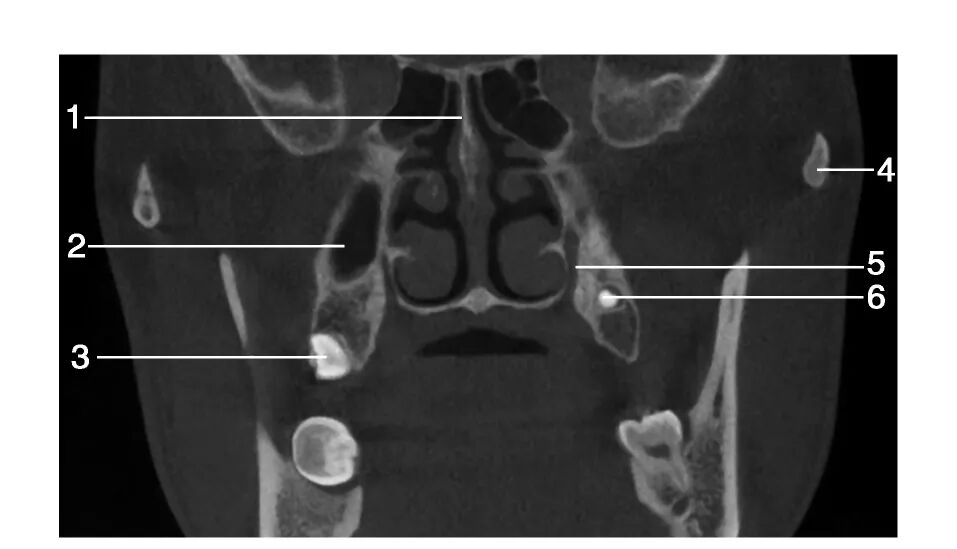

1.筛骨垂直板( perpendicular plate of ethmoid bone) ; 2.上颌窦( maxillary sinus) ; 3.右侧上颌第三磨牙( right maxillary third molar) ; 4.颧弓( zygomatic arch) ; 5.腭大管( greater palatine canal) ; 6.左侧上颌第三磨牙( left maxillary third molar)